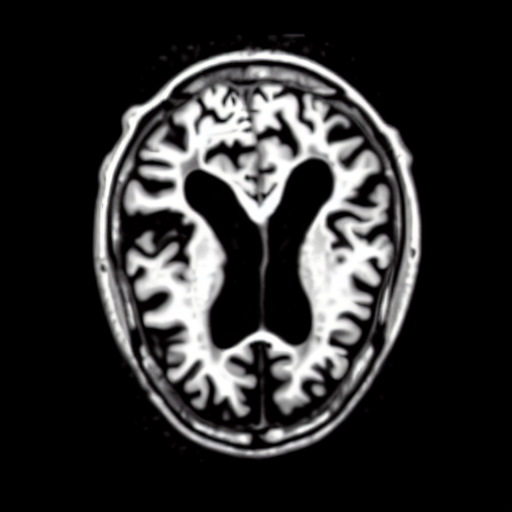

Qualitatively, Fig. 5 shows a significant improvement of the visual realism across all methods when using a drift of . The background is consistently black as in real brain MR images; the shape of the brain becomes more realistic, and the white and gray matter structure improves. For an analytical evaluation, we calculated the FID between our test data and 200 synthetically generated images from each method (100 CN, 100 AD). The results in Tab. 1 demonstrate that LD improves the ability of the model to generate realistic MRI slices for both healthy brains and brains with Alzheimer’s disease. For this reason, all following experiments were done with LD.

We use the Pix2Pix Zero model with a basic fine-tuned Stable Diffusion model to generate healthy brain MRIs from ones diagnosed with Alzheimer’s Disease and vice versa. We generate the counterfactual images by negating the ground truth label of the 200 test samples and conditioning the model on the negated label value and the source image. We compute image quality metrics, as well as the AUC, using a disease classification model trained on 600 real brain MRI slices (300 AD, 300 CN). Additionally, we determine the Structure Similarity Inced (SSIM) between the target and the source image to determine how well the identity of the source image is retained. The qualitative results in Fig. 6 , illustrate four examples from our two editing directions: from AD to CN and from CN to AD, respectively. When transitioning from AD to CN, the model primarily reduces the size of the ventricles. Conversely, in the CN to AD transformation, the ventricle size increases, accompanied by a worsening of brain atrophy.